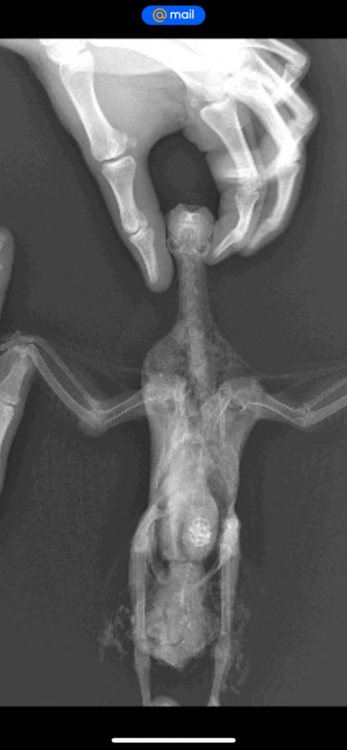

Здравствуйте. Неделю назад нашел голубя. Он просто лежал на спине и не мог встать. Подумал, что его на самокате сбили. Отвез к ветеринару, сделали рентген, который показал, что все норм. Вет.доктор который по птицам должен приехать в клинику через 5 дней. Пока взял его к себе. Он не мог стоять. Его косило и он падал опять на спину. Я его мыл, кормил и поил. Вот уже 4 дня как он стоит, ходит и нормально есть, и пьет. Но его все равно бывает наклоняет на правой бок. На крыле я заметил шишку. Наверное это область локтя. Почитал ваш форму и начал мазать ибупрофеном. Подскажите пожалуйста, что делать. Кто сталкивался с такой ситуацией. Вот симптомы: правое крыло нормально не складывается к спине, немного весит. Голубь бывает заваливается на спину через это же крыло. встать самостоятельно не может. Бывает трясется

рентген нужно чтобы посмотрела @Zosia